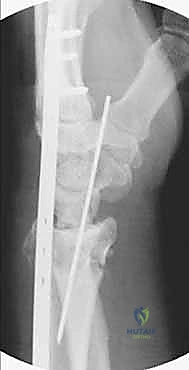

Fragment Mobilization and Fixation

Once liberated, the acetabular fragment is highly mobile. A heavy Schanz pin is inserted into the dense bone of the supra-acetabular region to serve as a joystick. The fragment is typically reoriented via a combination of flexion, internal rotation, and medialization.

Fluoroscopy confirms the correction, ensuring a normalized lateral center-edge angle, horizontal Tönnis roof, and appropriate anterior coverage without inducing retroversion (which could cause iatrogenic femoroacetabular impingement). Fixation is achieved using three or four fully threaded 3.5mm or 4.5mm cortical screws directed from the intact ilium into the mobilized fragment.